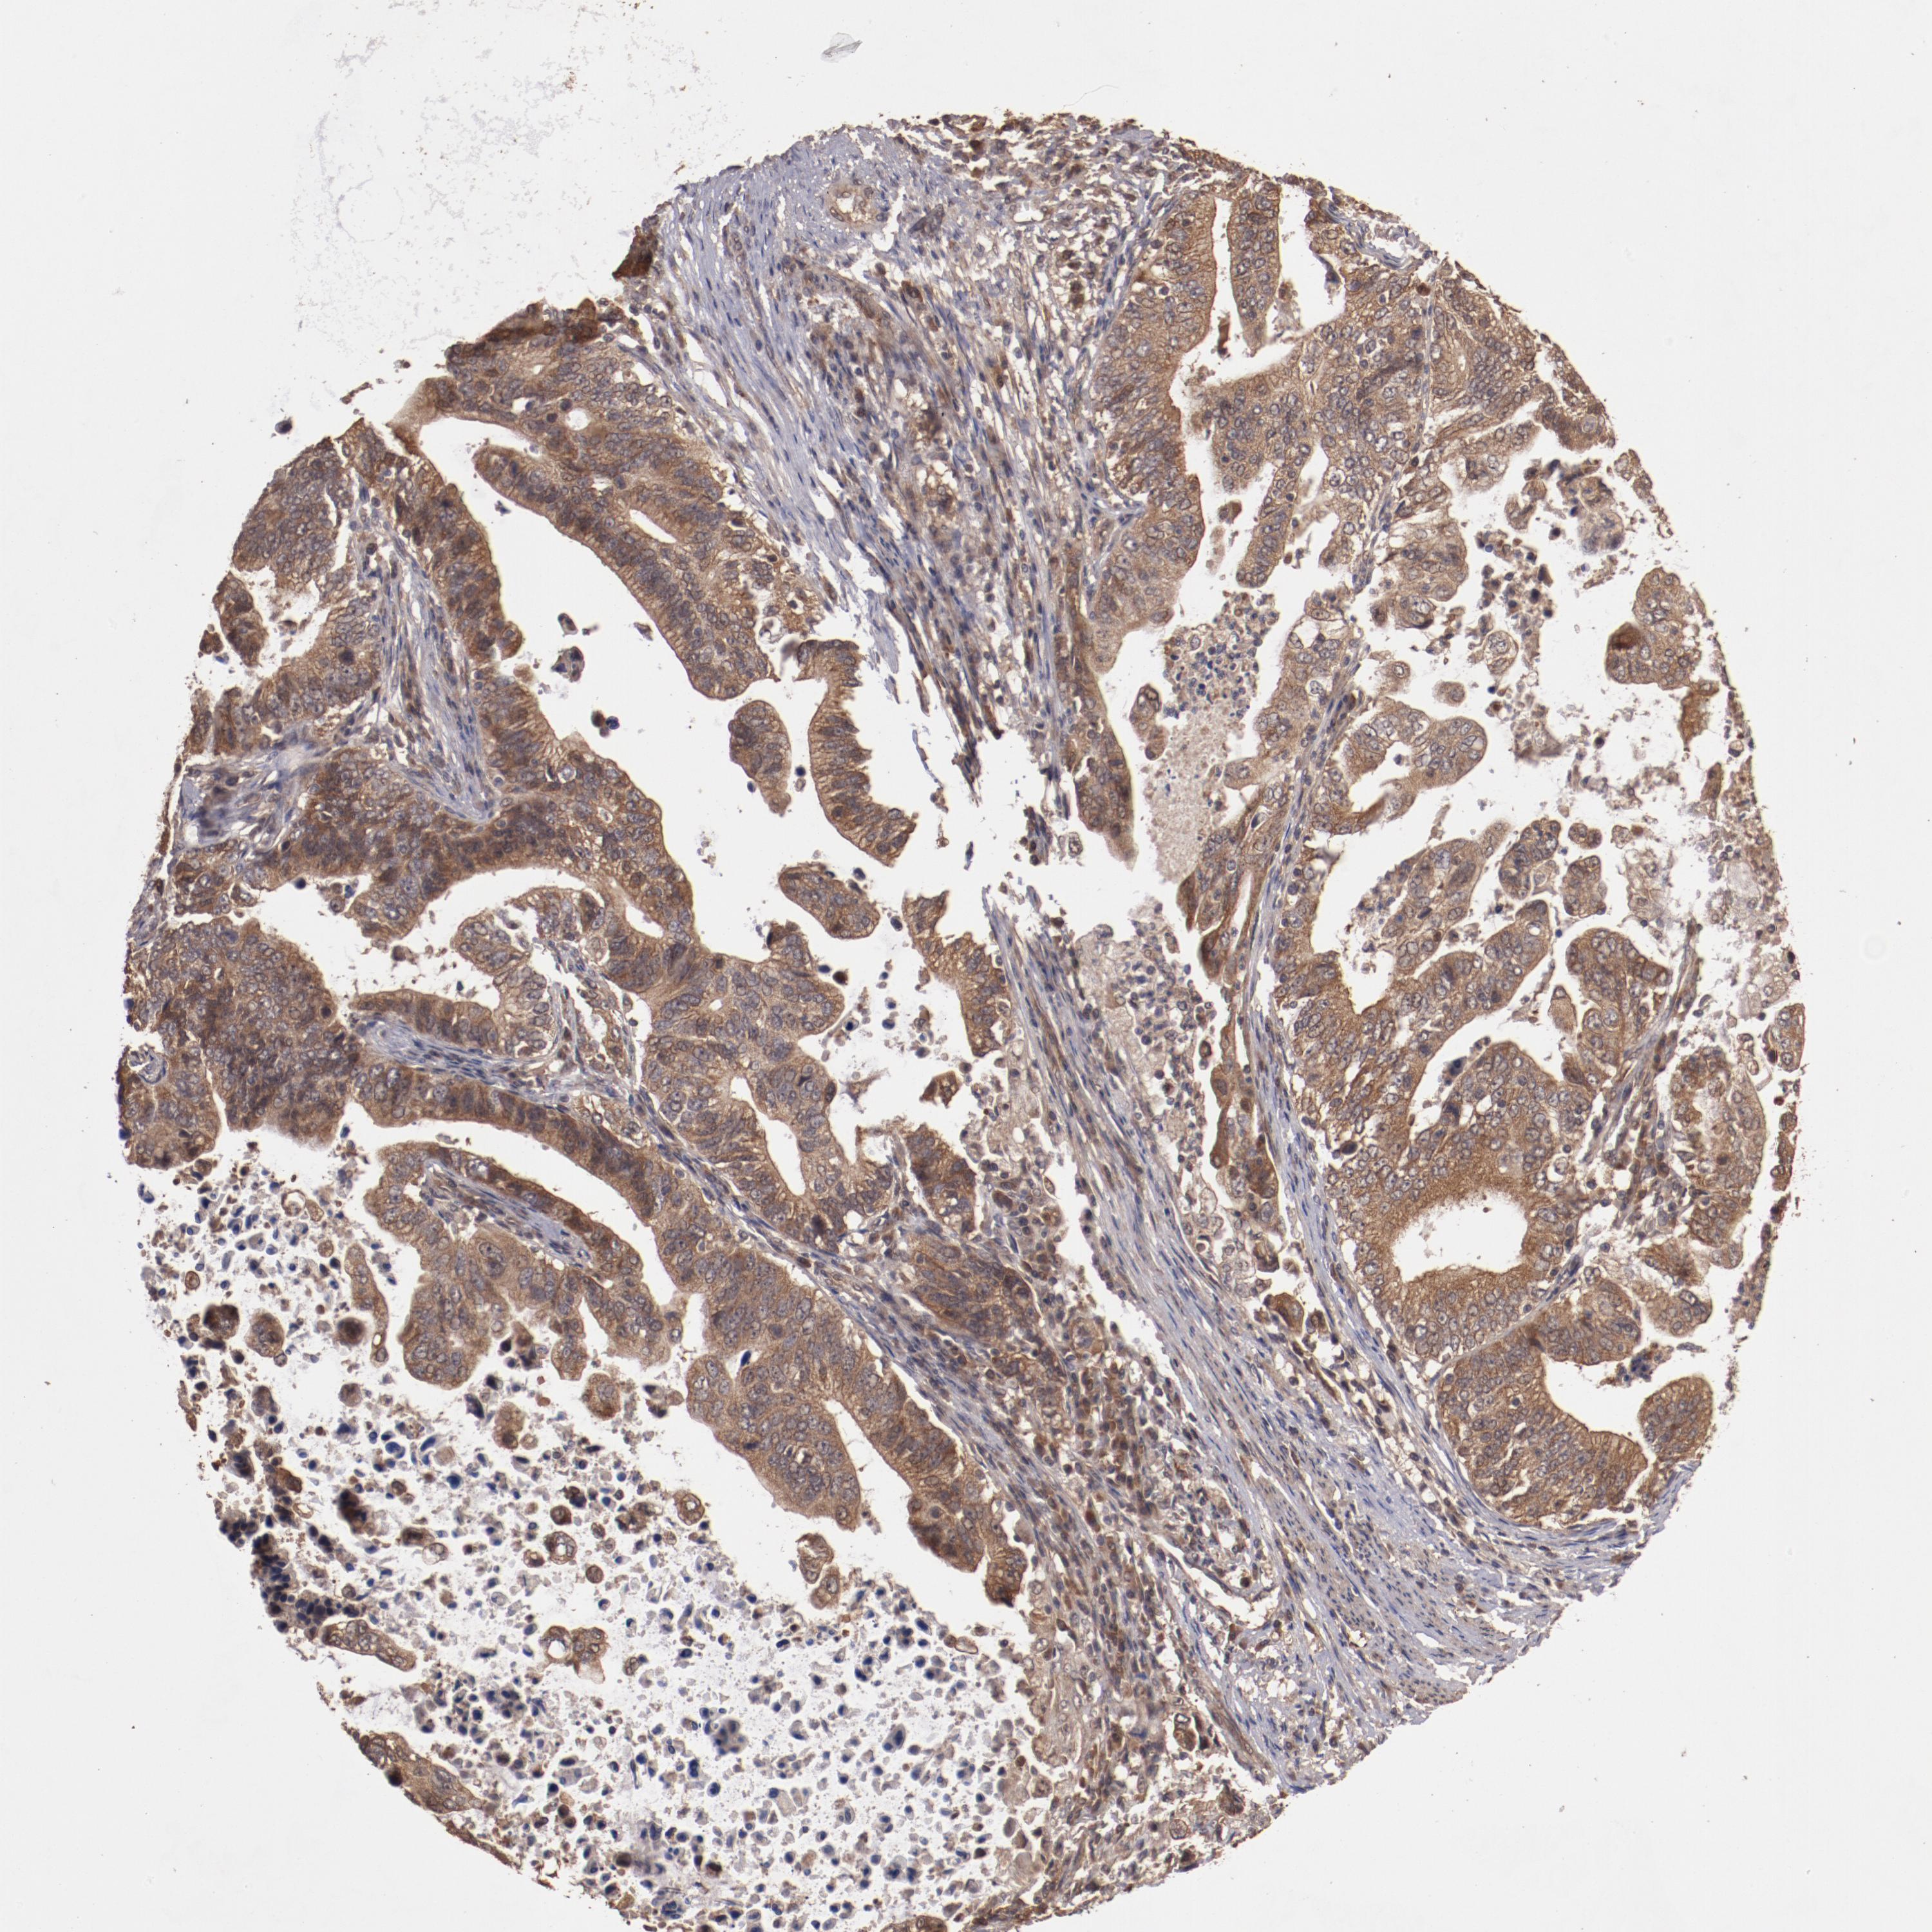

STOMACH CANCER - Protein expressioni

A mouse-over function shows sample information and annotation data. Click on an image to view it in a full screen mode. Samples can be filtered based on level of antibody staining by selecting one or several of the following categories: high, medium, low and not detected. The assay and annotation is described here.

Note that samples used for immunohistochemistry by the Human Protein Atlas do not correspond to samples in the TCGA dataset.

Antibody stainingi

Antibody staining in the annotated cell types in the current human tissue is reported as not detected, low, medium, or high, based on conventional immunohistochemistry profiling in selected tissues. This score is based on the combination of the staining intensity and fraction of stained cells.

Each image is clickable and will lead to virtual microscopy that enables deeper exploration of all samples and also displays staining intensity scores, fraction scores and subcellular localization as well as patient and tissue information for each sample.

Antibody HPA002543

Staining

High

Medium

Low

Not detected

Intensity

Strong

Moderate

Weak

Negative

Quantity

>75%

75%-25%

<25%

None

Location

Nuclear

Cytoplasmic/membranous

Cytoplasmic/membranous,nuclear

Adenocarcinoma, NOS